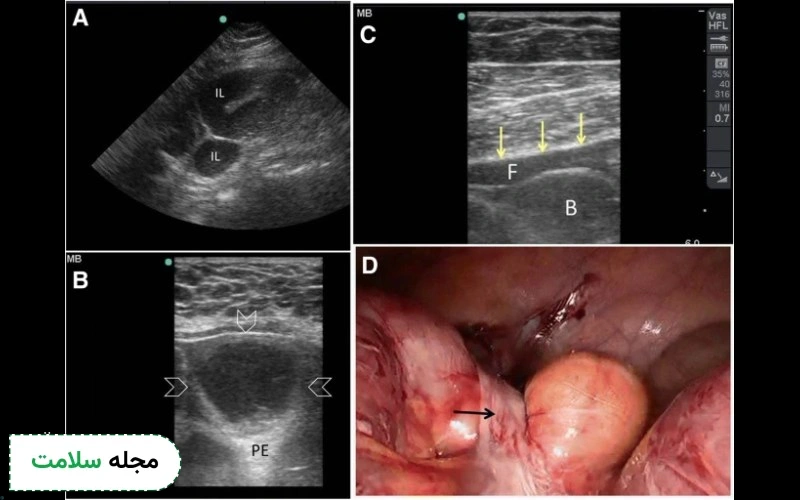

2. سونوگرافی اندورکتال/اندوآنال

سونوگرافی اندورکتال (EUS) از یک پروب خاص که به داخل مقعد وارد می‌شود استفاده می‌کند تا تصاویری با وضوح بالا از دیواره رکتوم و بافت‌های اطراف آن به دست آورد. این روش برای تشخیص مرحله سرطان رکتوم بسیار مؤثر است و به پزشکان این امکان را می‌دهد که عمق نفوذ تومور و گسترش آن به غدد لنفاوی مجاور را بررسی کنند.

تحقیقات نشان داده‌اند که EUS حساسیت بالایی برای شناسایی تومورهای مرحله اول رکتوم دارد و در مقایسه با سایر روش‌های تصویربرداری برای مرحله‌بندی محلی، به‌طور خاص مؤثرتر است.

3. سونوگرافی با کنتراست (CEUS)

سونوگرافی با کنتراست (CEUS) از میکروبابل‌ها به‌عنوان عوامل کنتراست برای بهبود تصویرسازی از جریان خون و تغذیه بافت در تومورها استفاده می‌کند. این تکنیک به‌ویژه برای شناسایی متاستازهای کبدی و ارزیابی پاسخ به درمان مؤثر است. استفاده از این روش باعث می‌شود که تصاویر دقیق‌تری از عروق تومور و ساختارهای اطراف آن به دست آید. مطالعات اخیر نشان داده‌اند که CEUS می‌تواند دقت تشخیص را به‌طور چشمگیری نسبت به سونوگرافی معمولی افزایش دهد.

4. سونوگرافی حین عمل

گاهی در طول جراحی برای ارزیابی گسترش سرطان روده به اندام‌های مجاور، به‌ویژه کبد، از سونوگرافی حین عمل استفاده می‌شود. با قرار دادن ترانسدیوسر به‌طور مستقیم روی کبد، جراحان می‌توانند تصاویر لحظه‌ای دریافت کنند که به آن‌ها کمک می‌کند تا احتمالات و روند جراحی را بهتر پیش‌بینی کرده و جلو ببرند. این تکنیک به‌ویژه برای شناسایی متاستازهایی که از طریق سایر روش‌ها قابل مشاهده نیستند مفید است و به برنامه‌ریزی جراحی دقیق‌تر می‌انجامد.